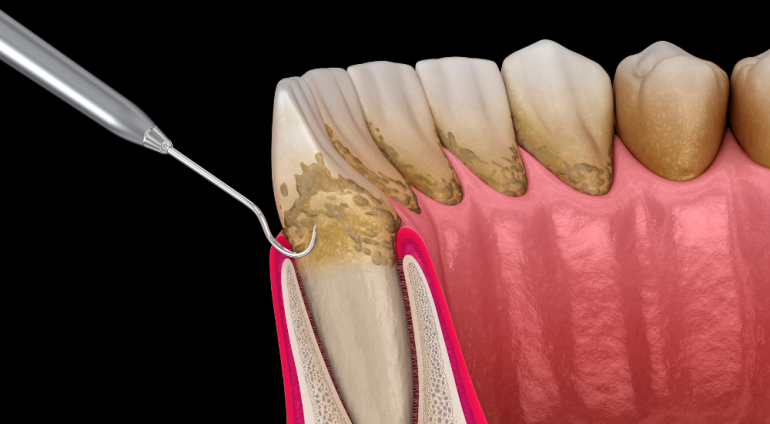

- SRP

麻酔をして、SRP(スケーリング、ルートプレーニング)によって、歯の根の表面に付着したプラーク、歯石を取り除きます。

SRP

SRPとは、歯の根元にまで入り込んだ歯石を取り除く処置です。歯周病の進行とともに深くなった歯周ポケットを改善できる可能性があります。

SRPとは、歯の根元にまで入り込んだ歯石を取り除く処置です。歯周病の進行とともに深くなった歯周ポケットを改善できる可能性があります。

成功すれば歯周病の進行を抑え、外科処置をせずに歯を残せる可能性がありますので、歯科医師からすすめられた際は受けていただくことをおすすめします。

SRPは、十分な訓練を受けた歯科衛生士が行いますのでご安心ください。